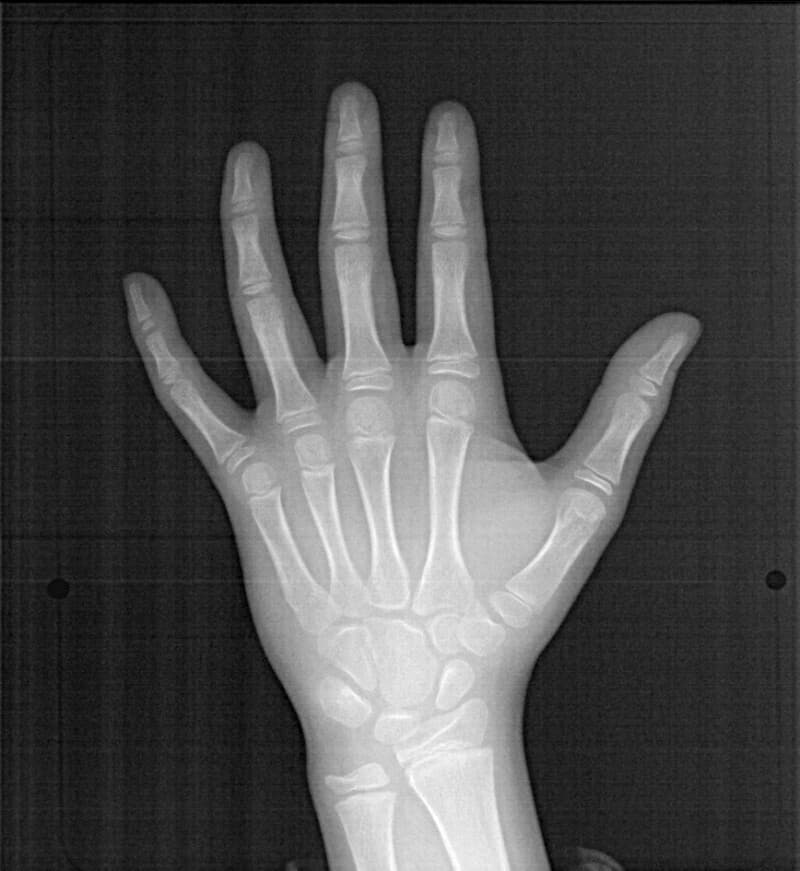

手根骨レントゲン分析結果:

口腔内やセファロ分析とは違い、今後の下顎の旺盛なgrowth(成長)を示唆しない像です。家族歴から考えても、極端に高身長ではないと予測されるので、将来外科矯正ケースになるリスクは実はさほど高くないと考えました。

セサモイドボーンも認められ、家族歴からも、今後の旺盛な下顎の成長の恐れがないと思われる所見です。